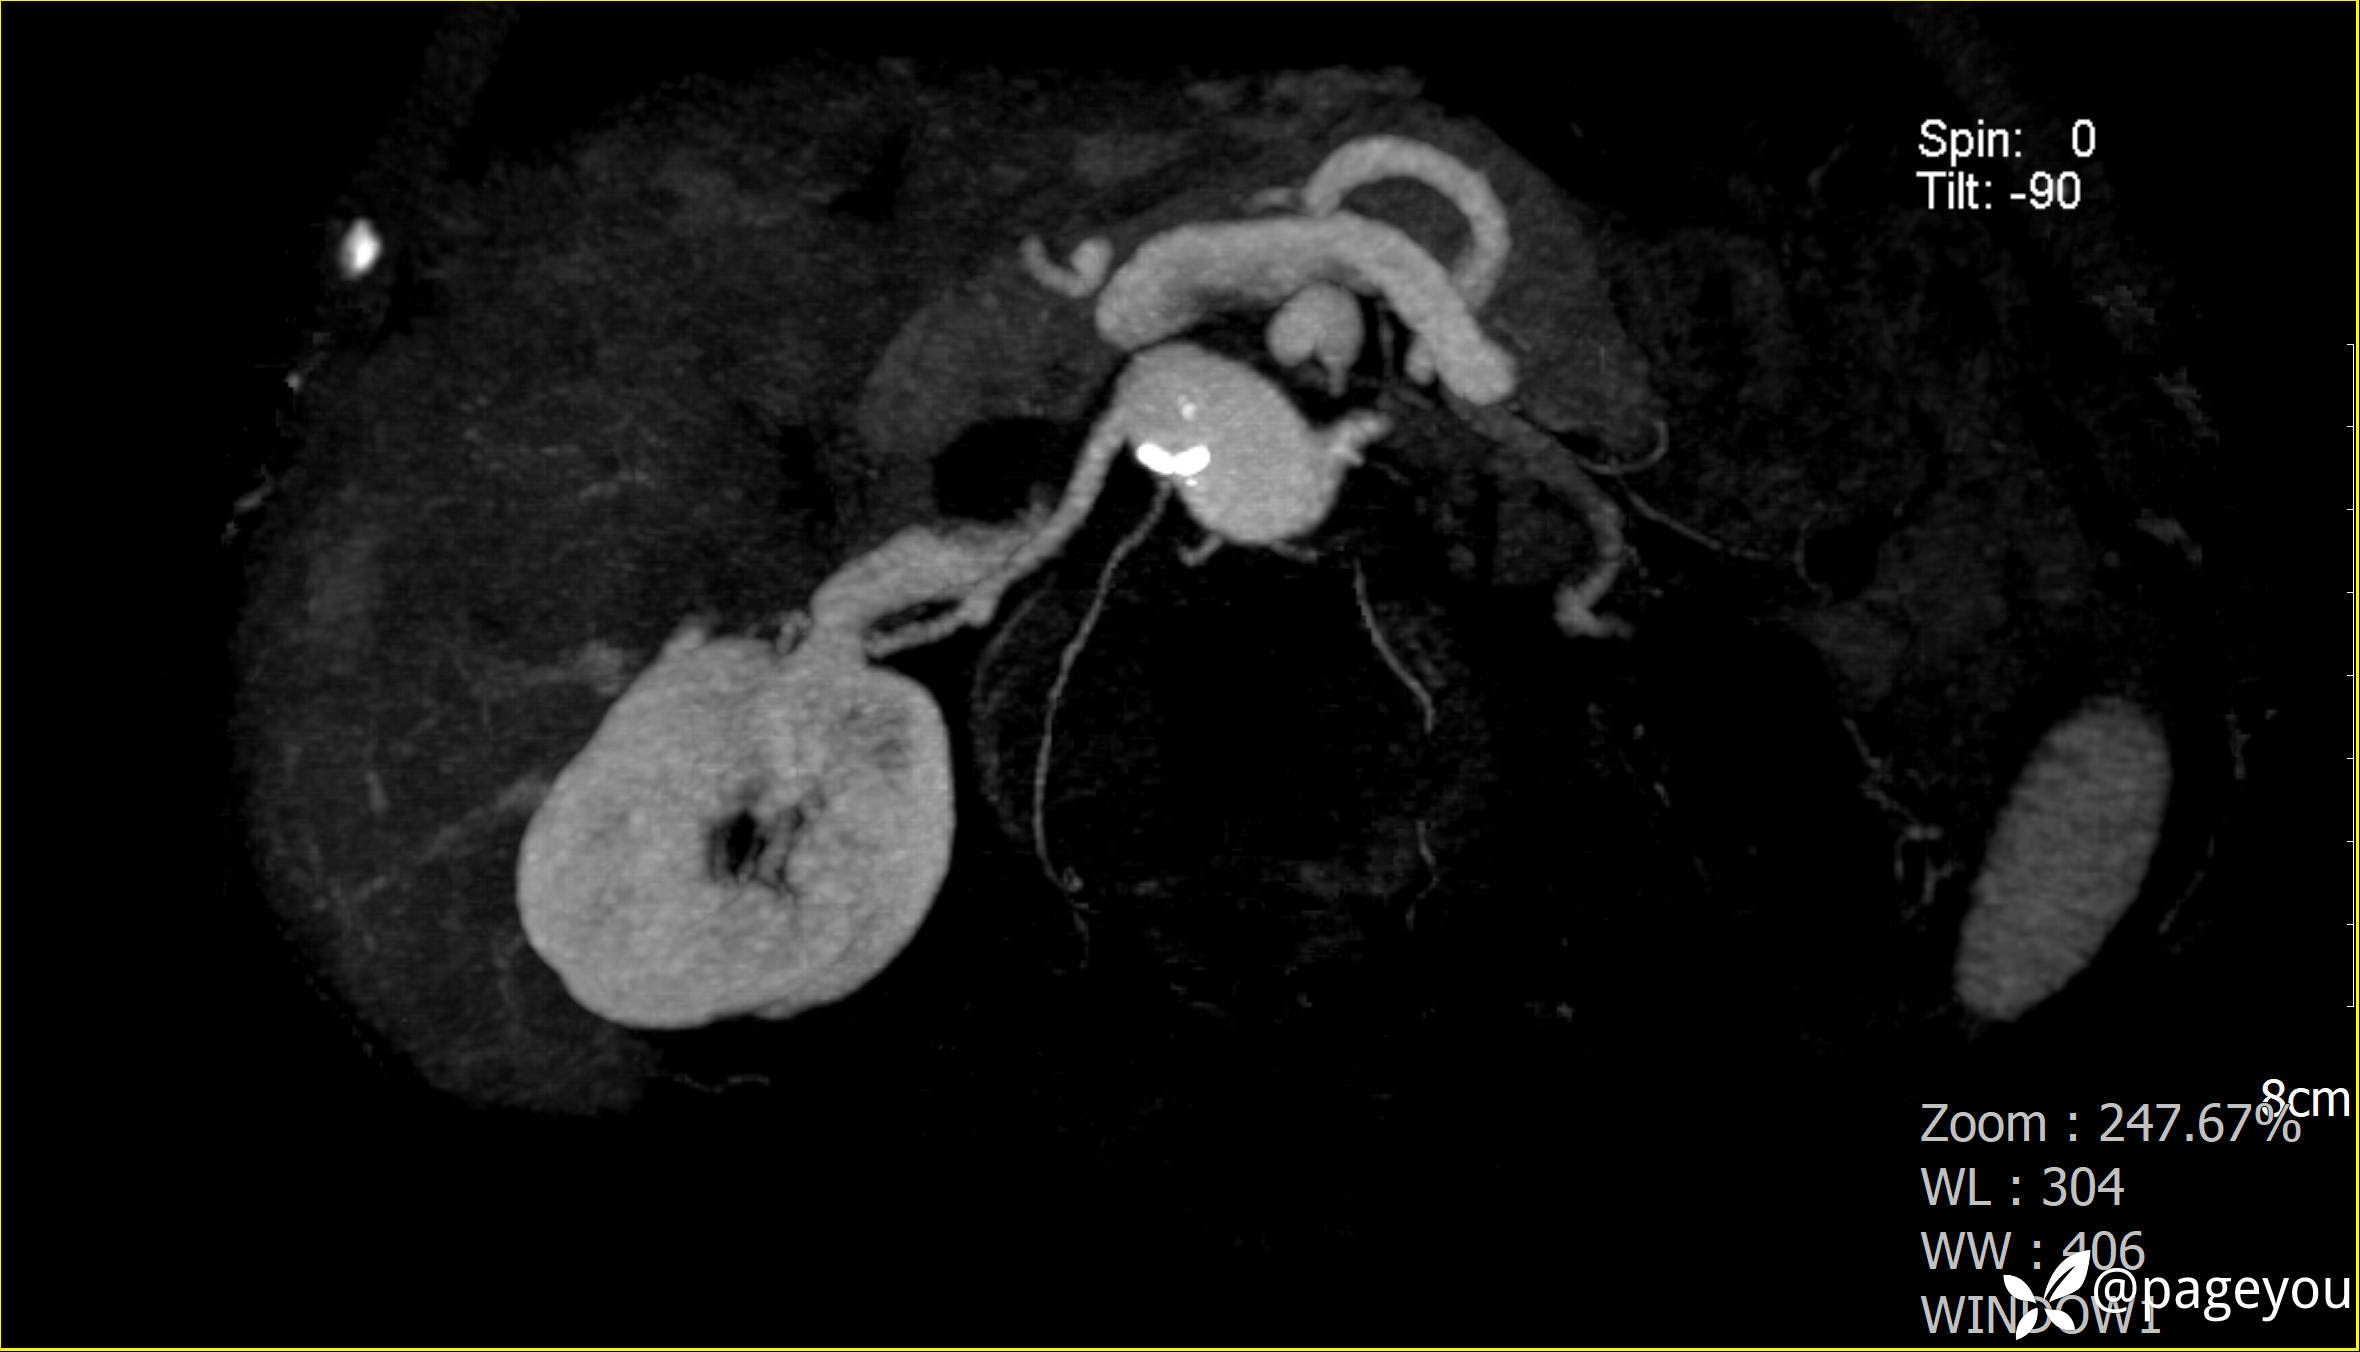

主动脉CTA: